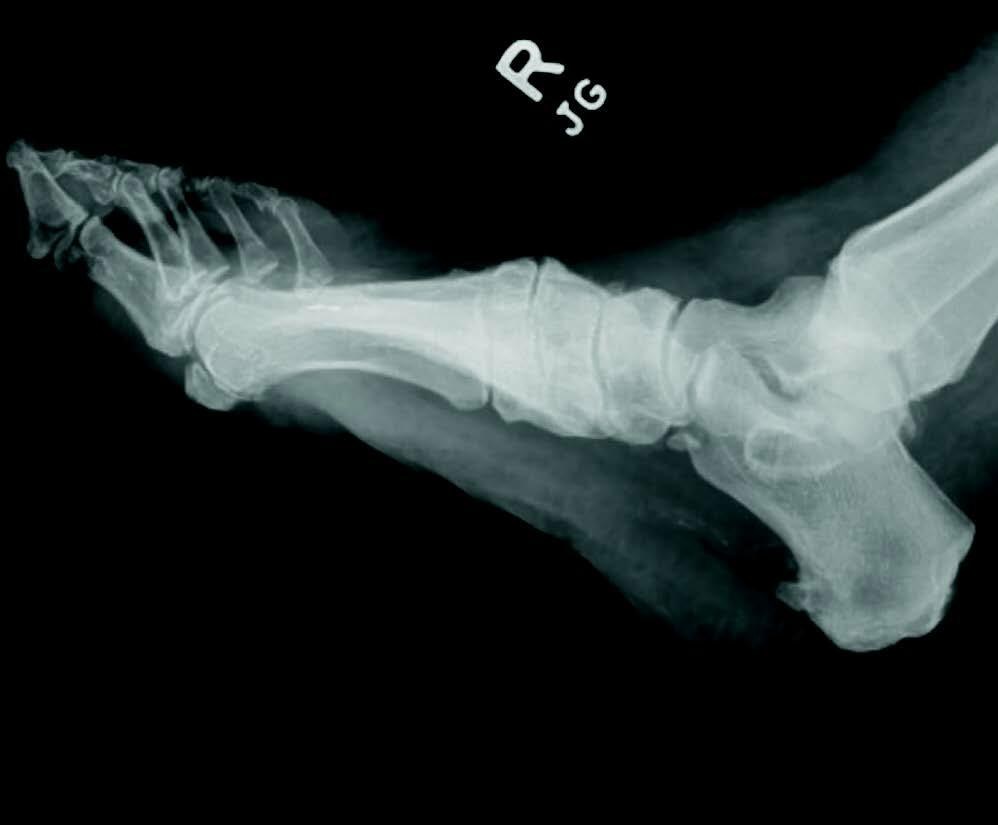

Charcot neuroarthropathy is a tissue-destructive process of the musculoskeletal system in patients with neuropathy.6-9 Most commonly affecting the foot and ankle, Charcot develops from repetitive trauma to an insensate foot. Historically, two theories describe the etiology of Charcot neuroarthropathy: the neurovascular theory; and the neurotraumatic theory. The neurovascular theory proposes that altered autonomics in patients with neuropathy leads to arteriovenous shunting and increased arterial flow, precipitating amplified osteoclastic activity and subsequent bone resorption and fracturing.10-11 The neurotraumatic theory suggests unrecognized trauma in neuropathic patients leads to repetitive injury and subsequent breakdown.12

Regardless of the cause, an acute Charcot foot is a hyperinflammatory event in the setting of immune dysregulation. Jeffcoate and colleagues hypothesized that Charcot foot developed due to the release of pro-inflammatory cytokines in an amplified immunologic response to trauma.12 They proposed a post-traumatic pathway that resulted in increased expression of TNF-α and IL-1ϐ. These cytokines induce increased expression of RANKL, which activates NF-κϐ (a transcription factor), mobilizing osteoclasts for osteolysis. Such a process would be a healthy response to injury, but in the setting of neuropathy, the injured site may sustain repetitive insults. Perhaps these repetitive insults manifest immune dysregulation, leading to an uncontrolled hyperinflammatory state.12-13 There is limited research to support this elegant theory, but there is acceptance of the proposed pathway as the most likely mechanism driving Charcot collapse.

Management of the acute Charcot foot involves management of any present ulceration or infection and aggressive offloading through immobilization to prevent progression of deformity and amplification of the inflammatory cycle.16-17 There is some early evidence to suggest using immunomodulators such as TNF-ɑ inhibitors in the management of acute Charcot foot.18 Bisphosphonates are occasionally part of the treatment for the acute Charcot foot with mixed results.19 Surgical management of the acute Charcot foot is rarely indicated as surgical trauma may worsen the inflammatory cascade, resulting in even more bone resorption.